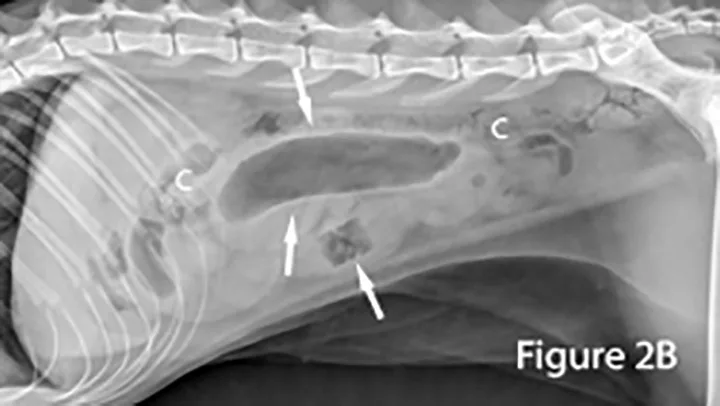

Markedly gas-distended segment of jejunum (arrows) measuring ~2.2 cm in diameter is present ventral to the feces-filled colon (C) in this cat. The foreign body (arrow) appears as an abnormal, rectangular, heterogeneous radiolucent (gas) structure. Note the presence of normal bowel.